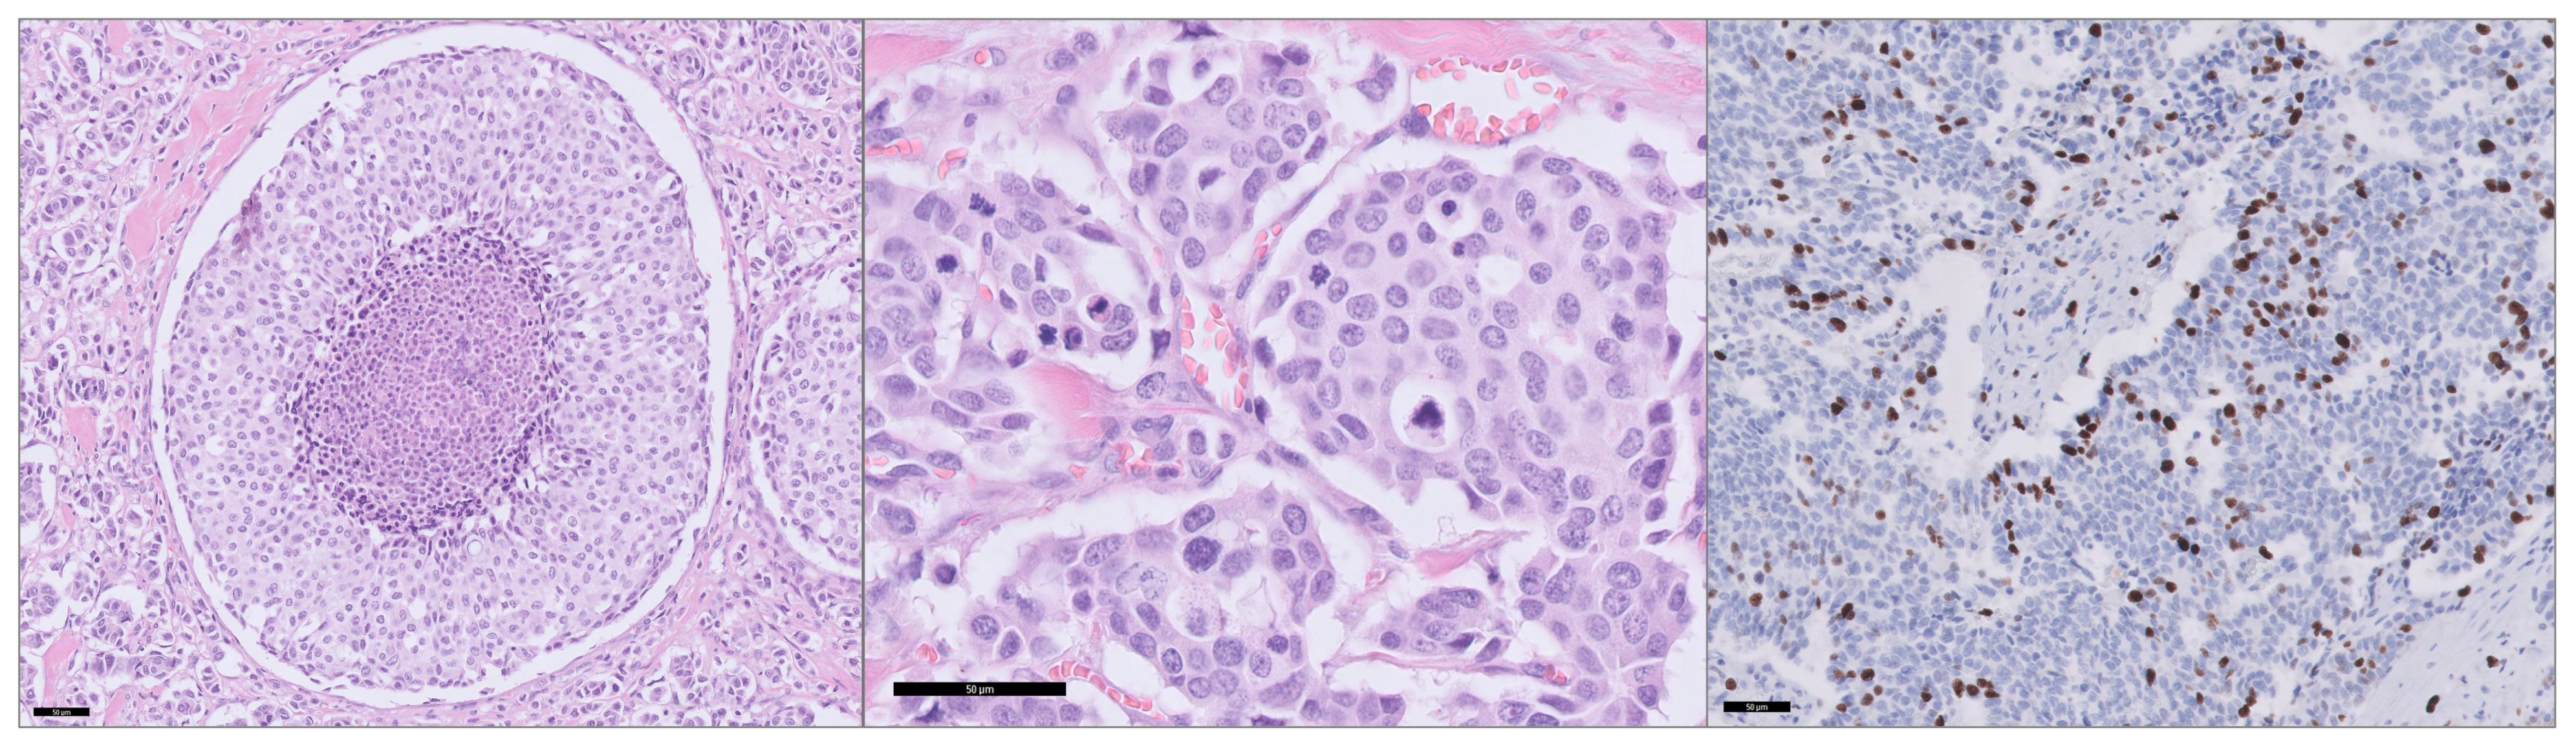

2.3. Histopathology and Construction of Tissue Microarray

2.6. Immunohistochemistry

2.7. Digital Scoring of Ki-67

2.8. Scoring of Biomarkers